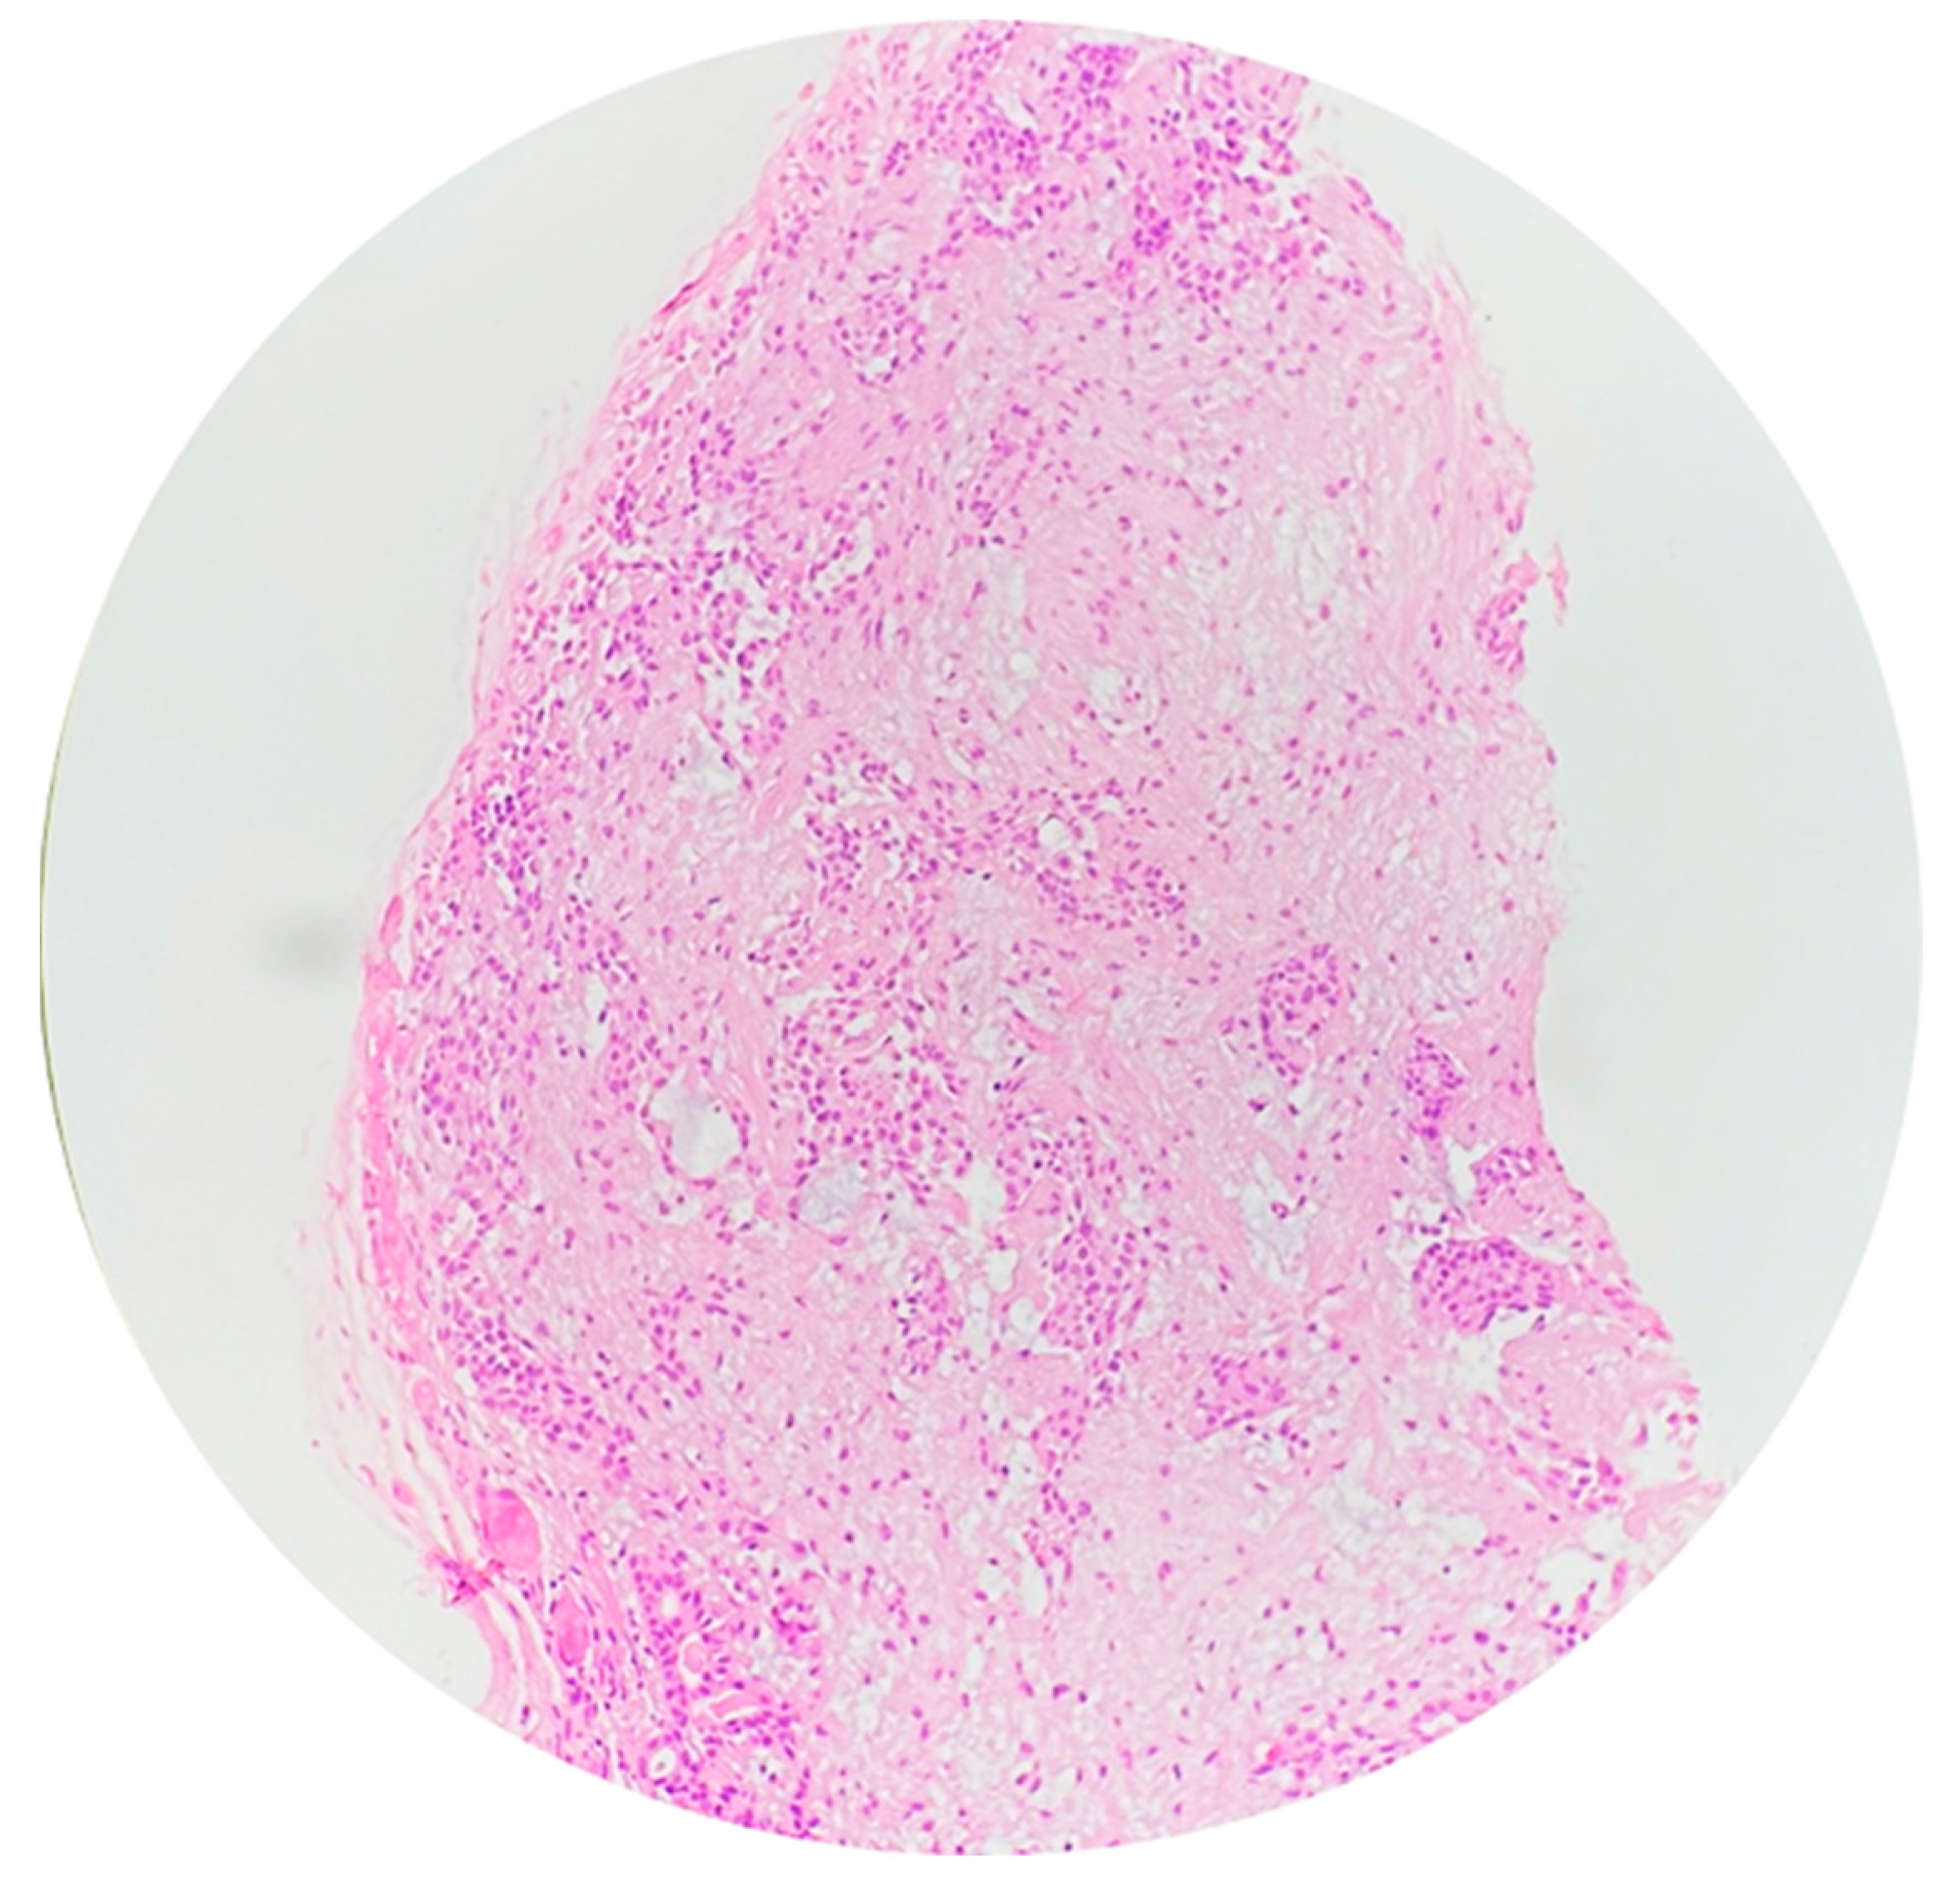

2.6. Histopathology